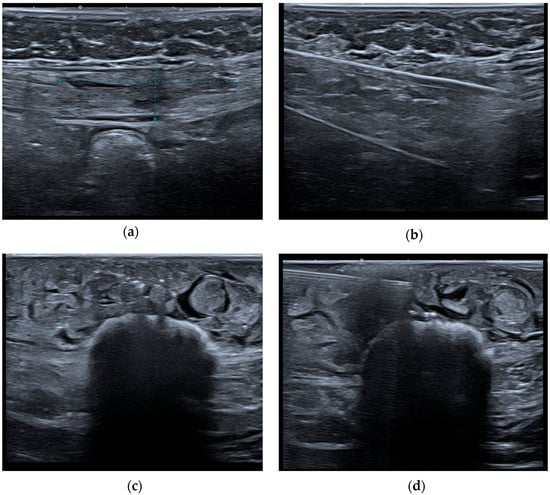

- Hensen, J.-H.J.; Van Breda Vriesman, A.C.; Puylaert, J.B.C.M. Abdominal Wall Endometriosis: Clinical Presentation and Imaging Features with Emphasis on Sonography. Am. J. Roentgenol. 2006, 186, 616–620. [Google Scholar] [CrossRef] [PubMed]

- Hu, S.; Liu, Y.; Chen, R.; Xiao, Z. Exploring the Diagnostic Performance of Magnetic Resonance Imaging in Ultrasound-Guided High-Intensity Focused Ultrasound Ablation for Abdominal Wall Endometriosis. Front. Physiol. 2022, 13, 819259. Available online: https://www.frontiersin.org/journals/physiology/articles/10.3389/fphys.2022.819259/full (accessed on 17 March 2025). [CrossRef] [PubMed]

- Busard, M.P.H.; Mijatovic, V.; van Kuijk, C.; Hompes, P.G.A.; van Waesberghe, J.H.T.M. Appearance of abdominal wall endometriosis on MR imaging. Eur. Radiol. 2010, 20, 1267–1276. [Google Scholar] [CrossRef] [PubMed]